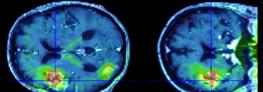

L’accident vasculaire cérébral (AVC ou, plus communément, attaque cérébrale, embolie cérébrale ou apoplexie) se caractérise par une lésion d’une partie du cerveau à la suite de l’obstruction d’un vaisseau (accident ischémique ou infarctus cérébral) ou par la rupture d’un vaisseau sanguin et l’accumulation d’une poche de sang (accident hémorragique ou hémorragie cérébrale). Environ 85 % des AVC sont d’origine ischémique et 15 % d’origine hémorragique.